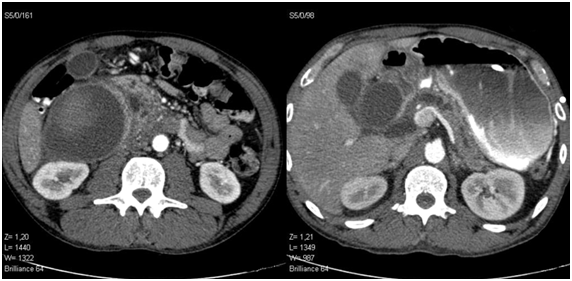

Contrast abdominal tomography was performed, showing pancreas with signs suggestive of chronic pancreatitis and pseudocyst, as well as bulky expansive formation on the wall of the duodenum compatible with hematoma (Figures 1). In digestive endoscopy, the mucosa was located in the posterior wall of the right-pyloric cavity to the edge of the second duodenal portion suggestive of extrinsic compression (Figure 2).

Figure 1 Tomography of the abdomen and pelvis with contrast showing pancreas with small dilatation and tortuosity of the main pancreatic duct and cystic formation at the head of the pancreas of about 3.5cm. Expansive formation in the lateral wall of the first and second duodenal portions, extending caudally to the right iliac fossa of about 16x10x8cm (650ml). The lesion was spontaneously hyper attenuating suggesting hematoma with recent bleeding.